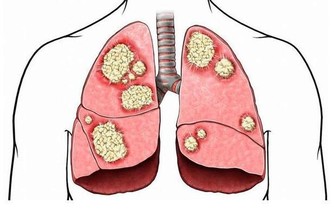

根據國健署調查,18歲以上糖尿病盛行率約為11.8%,截至今年糖尿病患人數已突破227萬人,

更高居十大死因第5名,在台灣每5名糖尿病患者就有1人死於心血管疾病,

是糖尿病患所有併發症中,發生率最高的疾病。